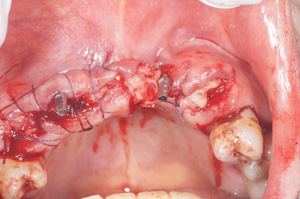

H.K‚³‚ñ 61Π —«@‰ïŽÐˆõ @Žèp“ú

‚Q‚O‚O‚X”N ‚RŒŽ‚Q‚V“úi‹àj  ãŠ{ƒm[ƒxƒ‹ƒKƒCƒhŽg—p@Ö¬“à’ÁÖ@•¹—p

@@@  @ ãŠ{ ‚R–{@”‚P‚U•” with Socket Lift and GBR   ’x‰„‰×d@

Nobel Speedy Groovy Rp ‚WD‚T mm

@@    @  @@@@@@@@”‚Q‚UE”‚Q‚V•”   ’x‰„‰×d

@   Rpl Tapered Wp ‚P‚O mm (‚Q–{)